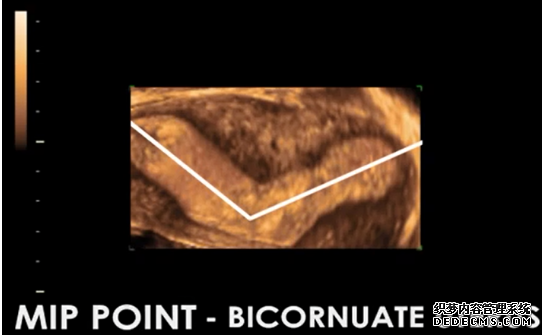

完美的最佳植入点定位技术。利用最新型的3D-4D辅助彩超技术,笙笙试管中心可以完美捕捉正常子宫、畸形子宫的最佳植入位点,为完美着床和完美受孕做好技术保障。